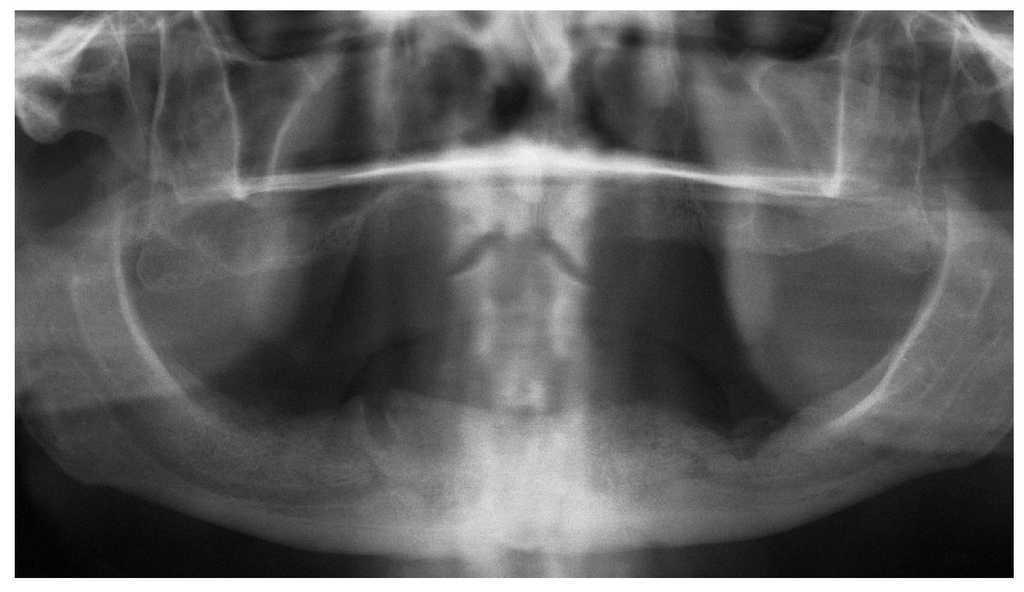

El signo clínico característico de la osteonecrosis asociada a bifosfonatos es un hueso de color blanco amarillento expuesto en el maxilar y/o en la mandíbula. El sondaje del hueso expuesto no suele provocar hemorragias y, por regla general, el paciente está asintomático22. No obstante, en áreas óseas extensas denudadas se pueden producir infecciones secundarias con un cuadro que incluye inflamación, producción de pus y dolor17. En pacientes dentados, la osteonecrosis imita a veces inicialmente un cuadro de periodontitis marginal. Después de la extracción, la cicatrización evoluciona de forma tórpida acompañada de una exposición ósea progresiva (figs. 1a a 1c). Una región afectada frecuentemente en la primera fase de la osteonecrosis asociada a bifosfonatos es la cortical lingual de la región de los terceros molares inferiores (figs. 2a y 2b). En los pacientes edéntulos se afectan a menudo zonas de la cresta alveolar maxilar y/o mandibular expuestas a la presión masticatoria directa de las prótesis totales (figs. 3a a 3c, 4a y 4b).

Figura 2a. Radiografía panorámica de un paciente de 69 años sometido a tratamiento con bifosfonatos intravenosos (Zometa) y a tratamiento concomitante con corticosteroides (ambos desde 2004) por un carcinoma de próstata metastatizado. En diciembre de 2006 le fue exodonciado el diente 37 por el odontólogo de cabecera. El paciente fue remitido a nuestra clínica en junio de 2007 por una falta de cicatrización del alvéolo varios meses después de la intervención.

Figura 2b. En la primera exploración en julio de 2007 destacó la presencia de un secuestro óseo expuesto en la región 37 en vestibular. La región osteonecrótica era indolora y la única molestia que percibía el paciente se debía al borde óseo afilado.